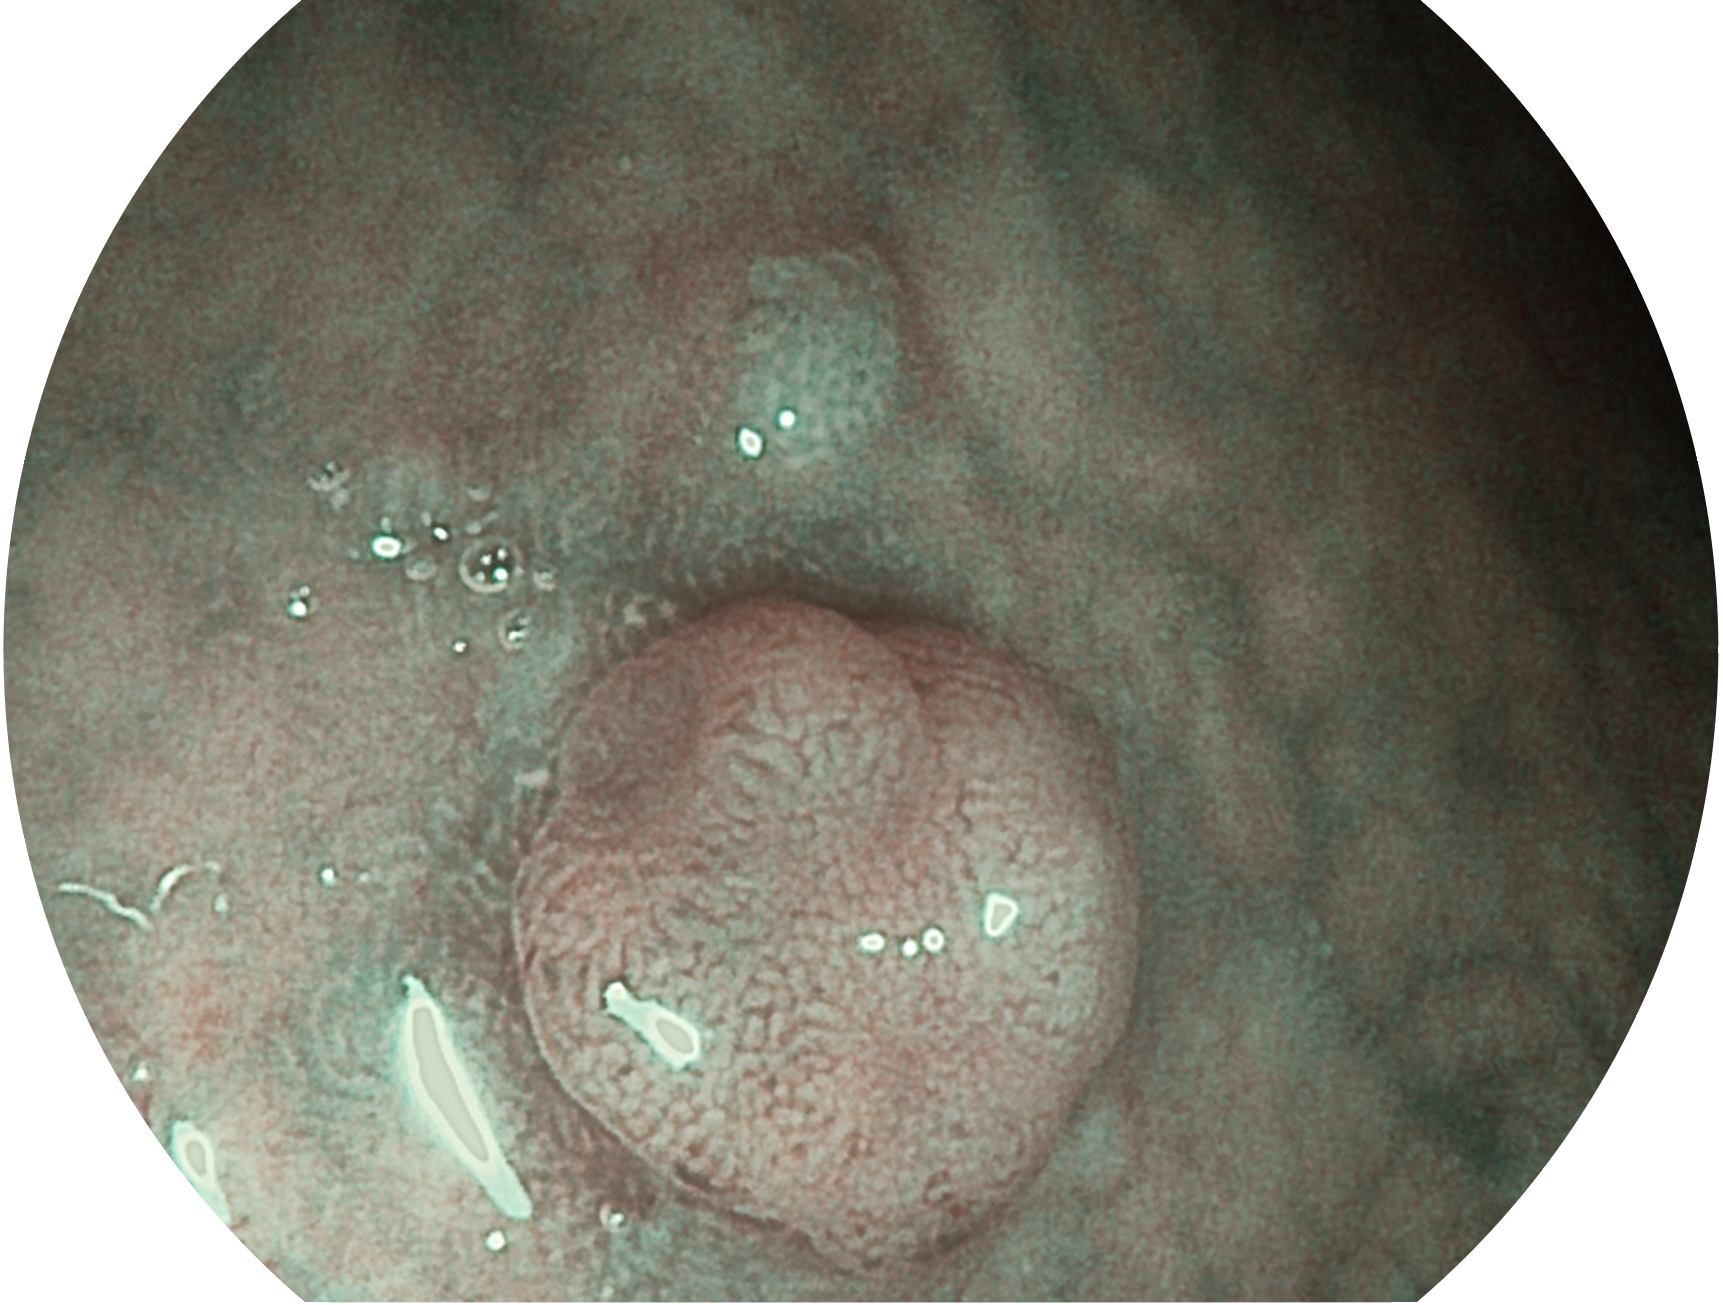

• 白光图像 SFI图像